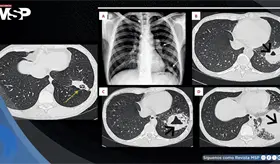

El tabaquismo y la exposición a contaminantes son los principales factores de riesgo, aunque también hay causas genéticas.